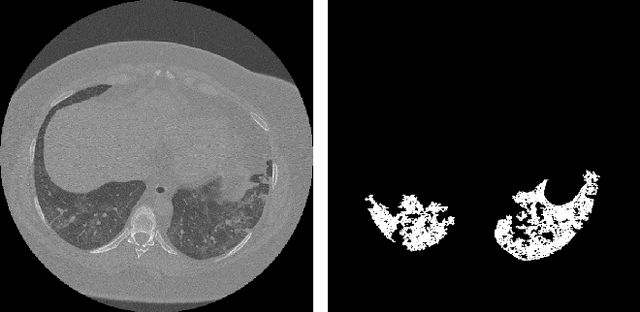

Abstract:Analysis of chest CT scans can be used in detecting parts of lungs that are affected by infectious diseases such as COVID-19.Determining the volume of lungs affected by lesions is essential for formulating treatment recommendations and prioritizingpatients by severity of the disease. In this paper we adopted an approach based on using an ensemble of deep convolutionalneural networks for segmentation of slices of lung CT scans. Using our models we are able to segment the lesions, evaluatepatients dynamics, estimate relative volume of lungs affected by lesions and evaluate the lung damage stage. Our modelswere trained on data from different medical centers. We compared predictions of our models with those of six experiencedradiologists and our segmentation model outperformed most of them. On the task of classification of disease severity, ourmodel outperformed all the radiologists.